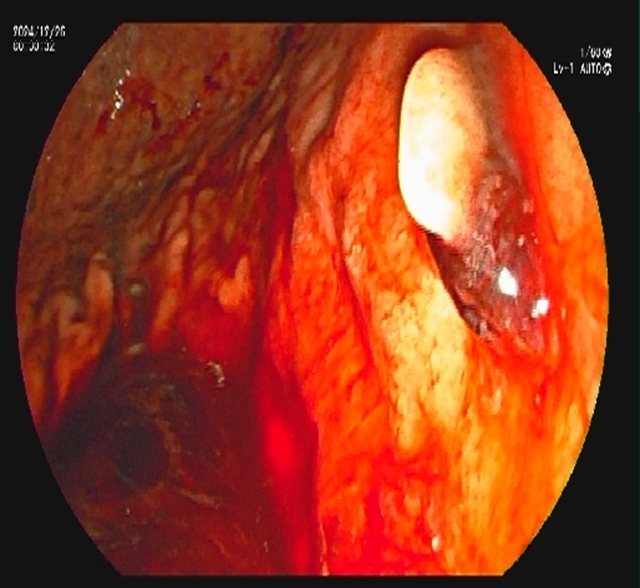

内镜到达十二指肠乳头时,切开乳头的瞬间,大量白色脓液喷涌而出(证实胆道高压、感染极重);随后用球囊扩张乳头(扩大开口),顺利取出嵌顿的结石。

术后,放置鼻胆管持续引流脓性胆汁(当天引出300ml浑浊胆汁)。